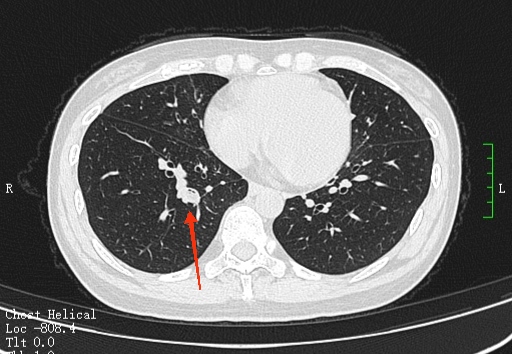

龚女士入院后,医生查看她的CT结果发现,龚女士病人右中叶支气管内有异物,为其安排了支气管镜检查,果然发现气道异物,揪出一块“辣椒皮”,辣椒皮周围已经形成增生的肉芽肿,而且有大量的化脓性感染,咳嗽半年多的罪魁祸首终于被找到。经过询问,龚女士仔细回忆,在半年前有次吃宵夜,是有呛咳的情况,但当时也没有多在意。